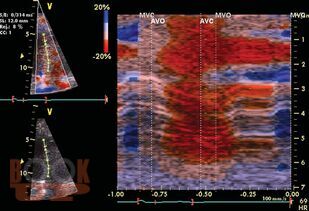

Книга посвящена ультразвуковым методам оценки и диагностики деформации миокарда: допплеровской визуализации тканей и технологии двухмерного отслеживания пятен серой шкалы ультразвукового изображения миокарда. Представлены возможности оценки вращения и скручивания левого желудочка на основе технологии двухмерного отслеживания пятен серой шкалы ультразвукового изображения миокарда. Приводятся нормальные значения показателей деформации миокарда левого желудочка, а также данные об изменениях показателей деформации миокарда и скручивания левого желудочка при разнообразных патологических и некоторых физиологических состояниях, таких как гипертрофия желудочков, сердечная недостаточность, инфаркт миокарда, пороки сердца и кардиомиопатии. Обсуждаются вопросы дифференциальной диагностики с использованием показателей деформации миокарда. Освещается прогностическое значение показателей деформации миокарда и скручивания левого желудочка. Представлены основные ограничения методов.